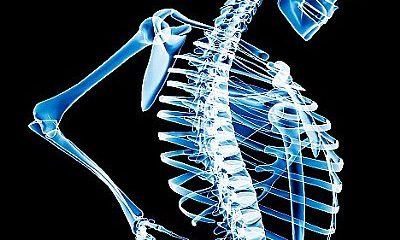

Para combater o subdiagnóstico da osteoporose no sexo masculino, os homens são o foco da campanha internacional “Ame seus ossos”, pelo Dia Mundial da Osteoporose, nesta...